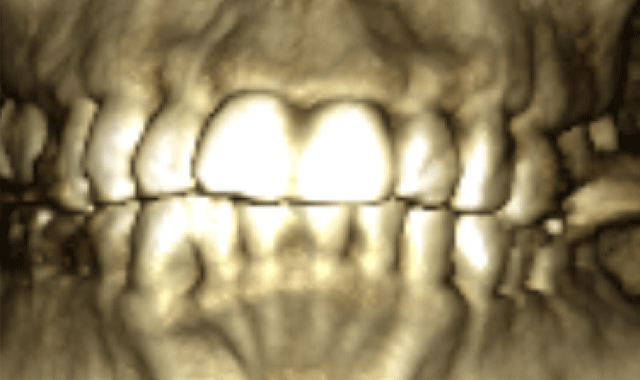

The initial scan was taken with a 400 μm voxel size at 90 kV, a 10 mA setting. The scanning time was 13.887 seconds. The machine used was a Planmeca ProMax 3D Mid. The radiograph in Figure 1 has a thickness of 5.2 mm. Though the alveolar housings are thin, the teeth seem to be well encapsulated in bone. Figure 2 is the 3D construction of this same area. A LFOV progress scan (dental only) was taken to evaluate the root alignments. The scan was taken at a 200 μm voxel size, 90 kV, 5 mA, in 4.044 seconds.

Fig. 2